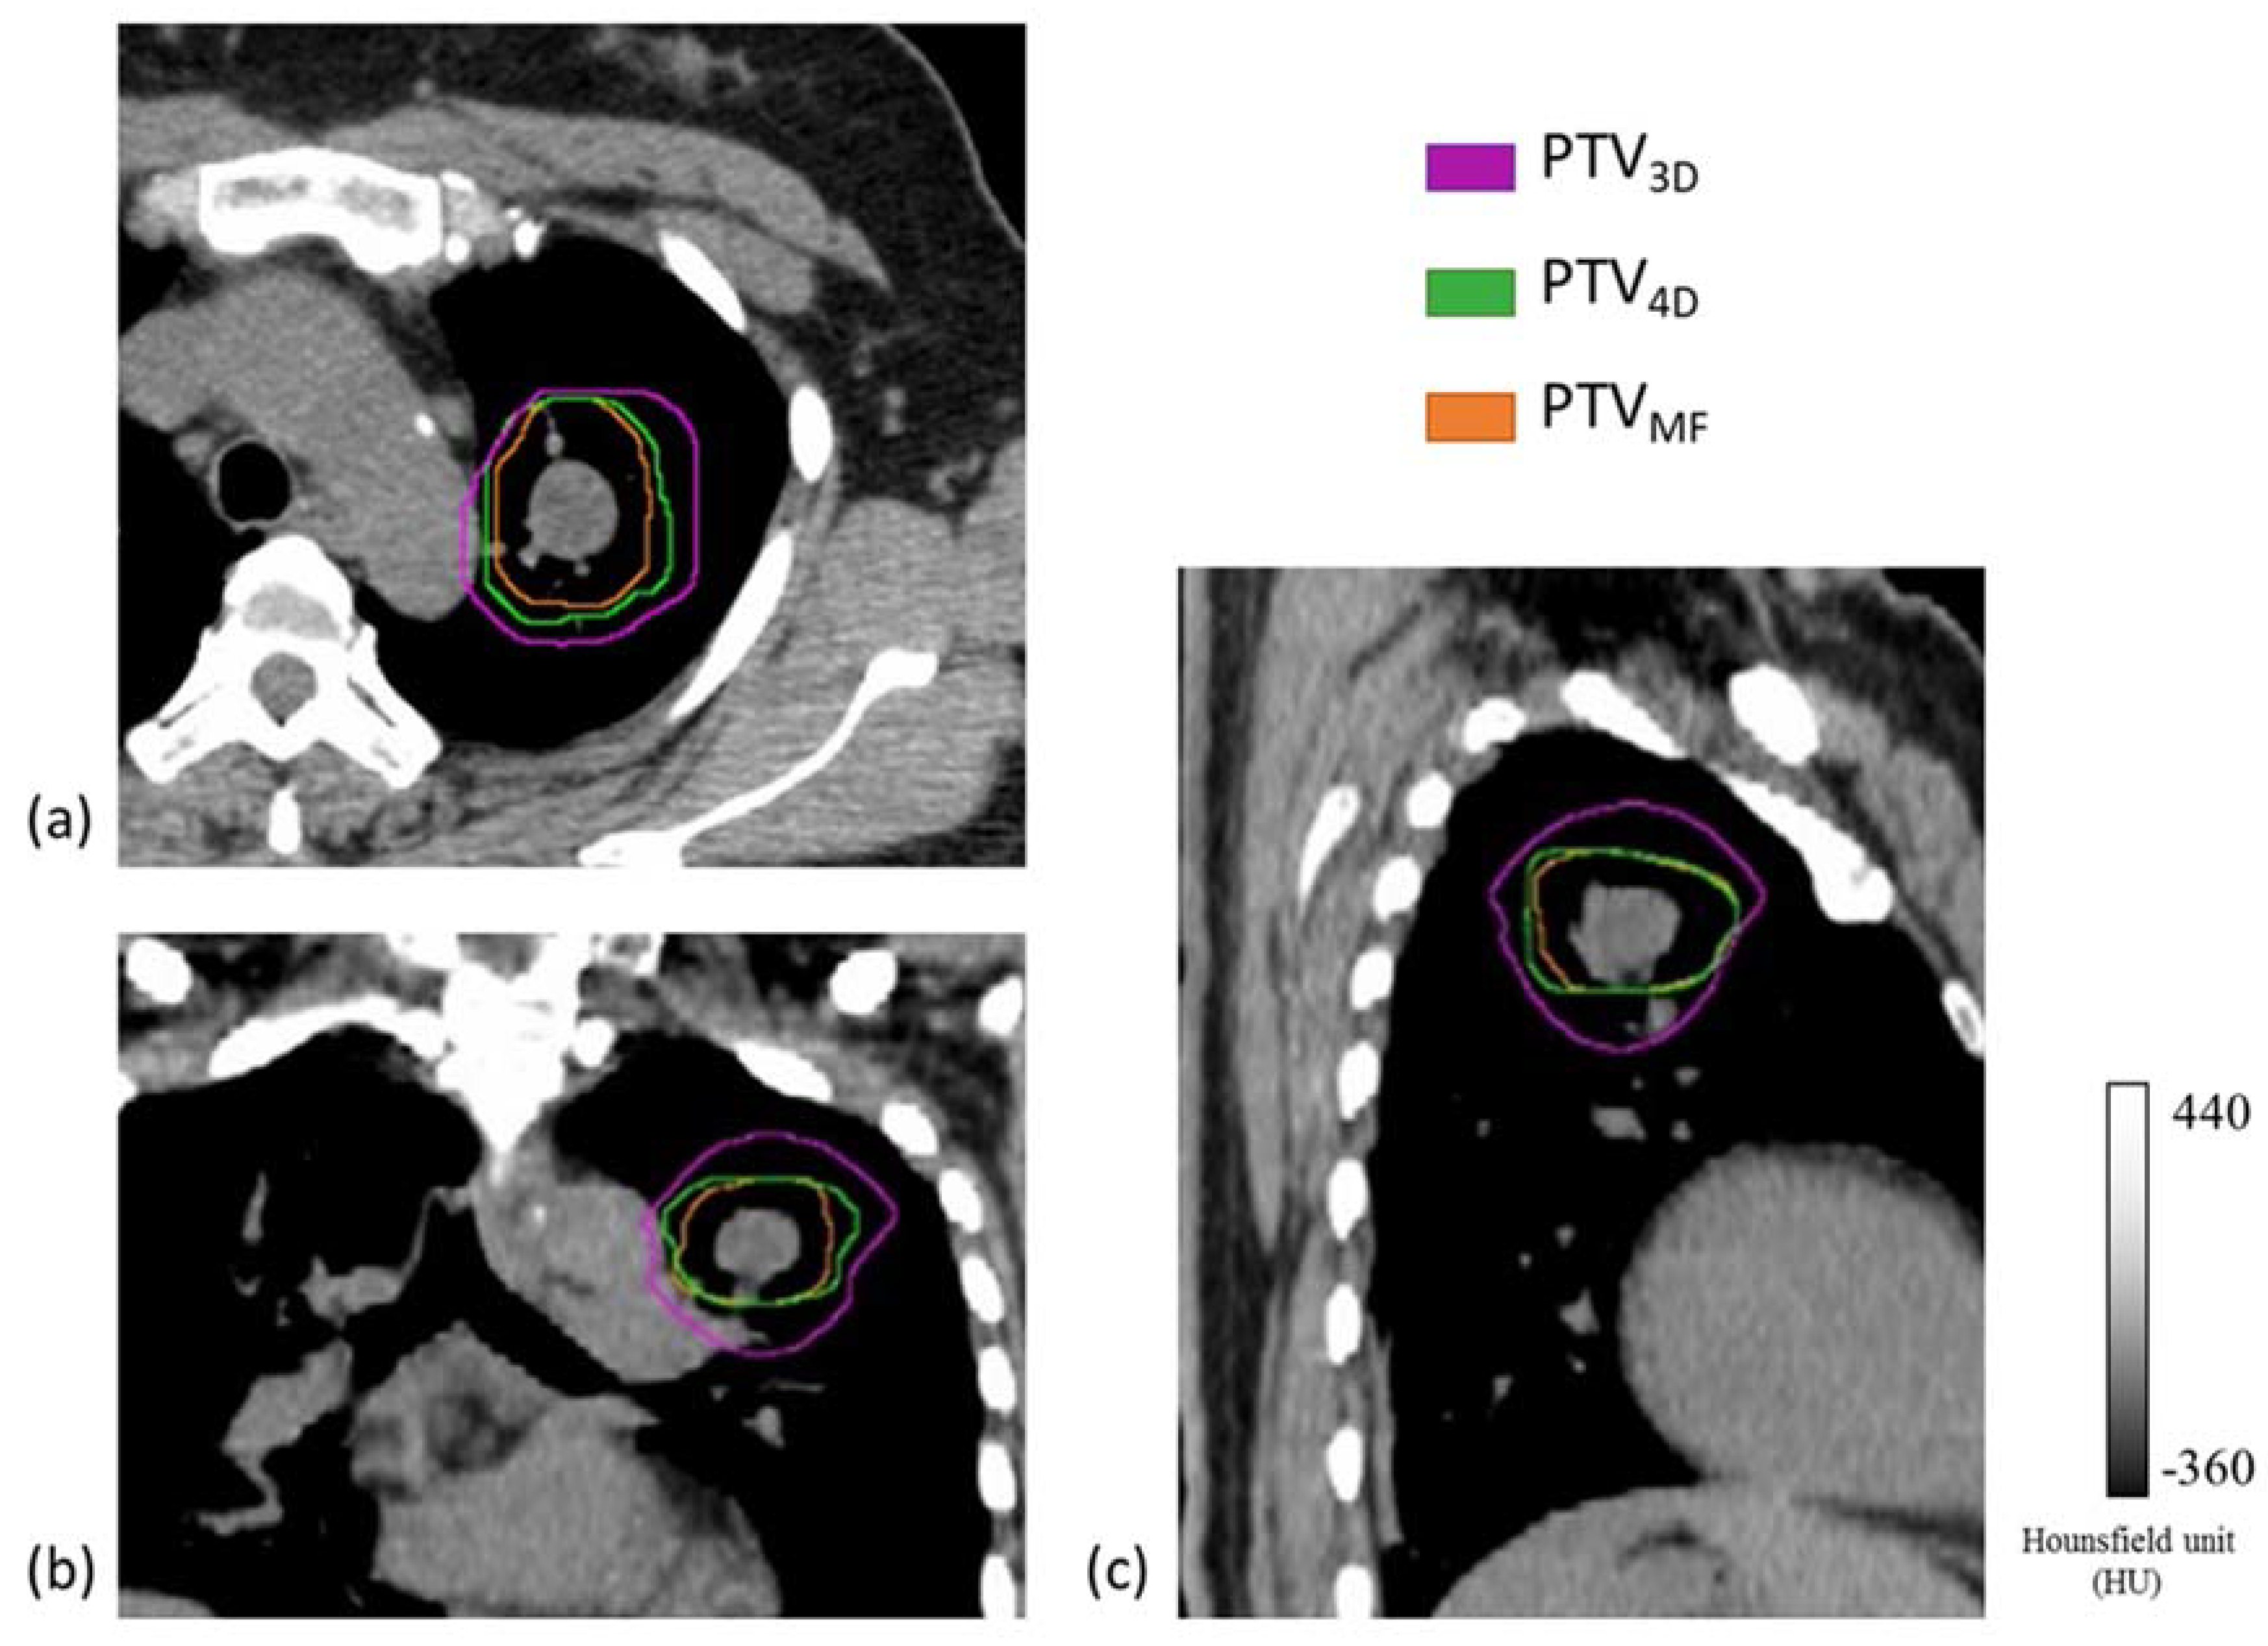

We next compared the percentage difference in PTVs between the treatment plans (Table 5). Between PTV3D and PTV4D, a maximum percentage difference of 55.3% was observed, with a median value of 35.6%; between PTV3D and PTVMF, the maximum percentage difference and the median were 74.1% and 40.6%, respectively; and between PTV4D and PTVMF, the maximum percentage difference and the median were 44.7% and 5.6%, respectively. Delineation of PTVs on CT images in the three treatment plans and their differences are shown in Figure 2.

Figure 2. Planning target volumes (PTVs) delineated on computed tomography (CT) images in different treatment plans for respiratory-gated radiation therapy. (a) Transverse, (b) coronal, and (c) sagittal sections of the chest. The purple line represents the PTV3D of the 3D Plan; the green line represents the PTV4D of the 4D Plan; and the orange line represents the PTVMF of the MF-Plan.

After ITV delineation, a 5-mm margin was added to create the PTV of each treatment plan, namely PTV3D, PTV4D, and PTVMF, respectively. OARs, such as the heart, lungs, and spinal cord, were delineated by an experienced radiation oncologist based on the CTMIP images.